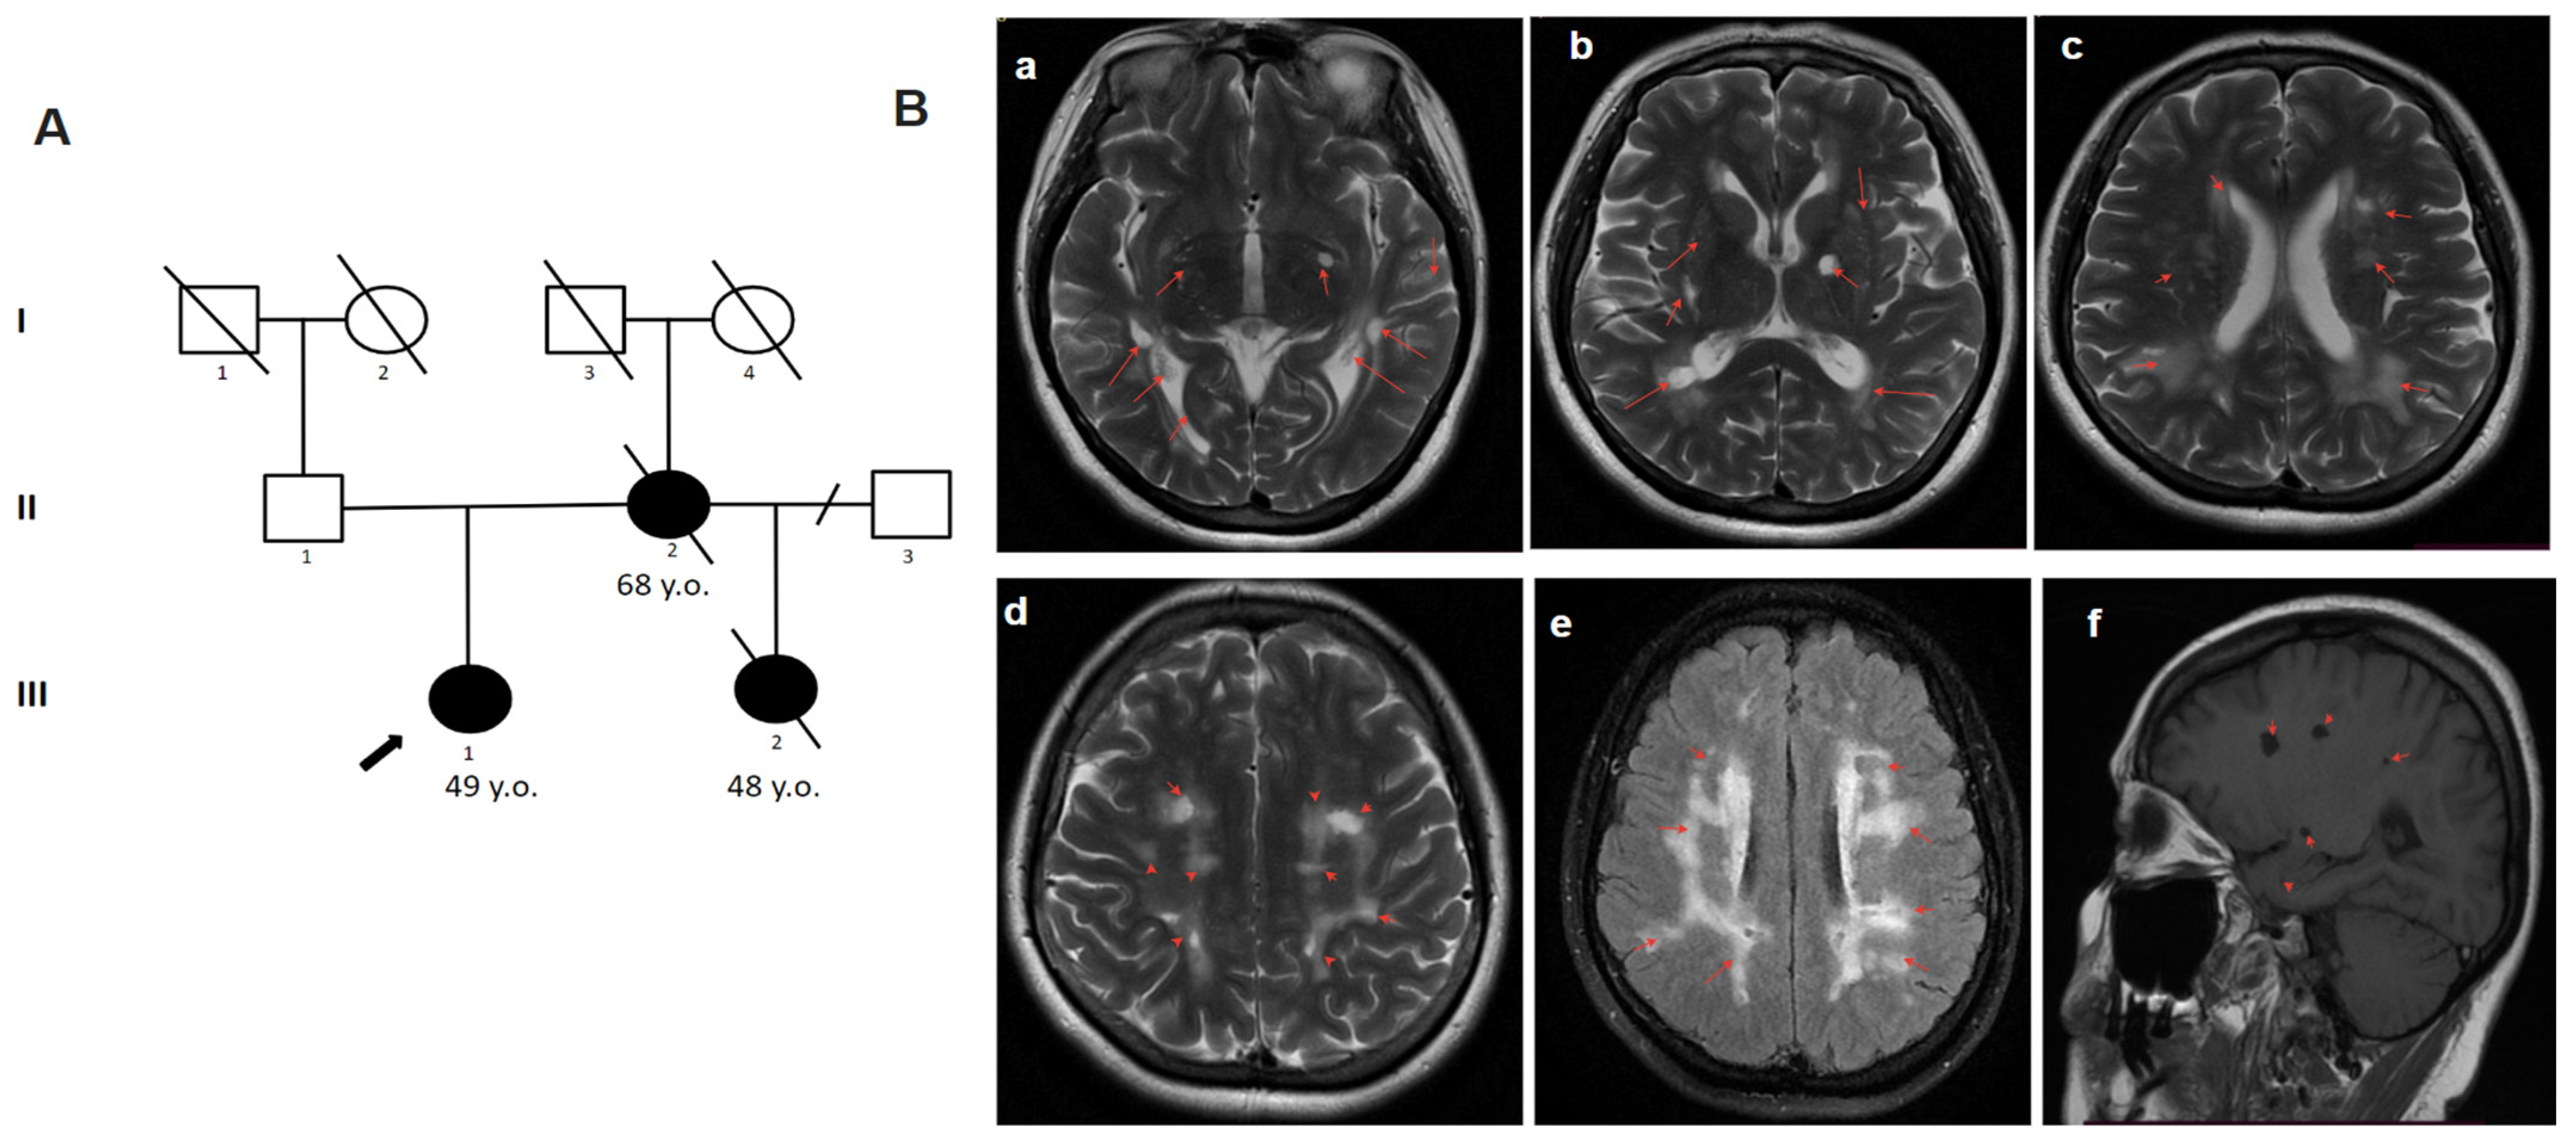

2.4.3. Patient 3

2.4.4. Patient 4.1